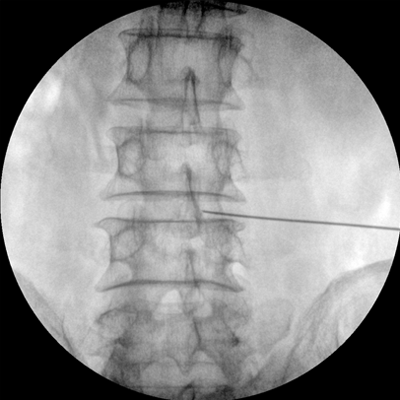

Clinical picture

臨床圖片